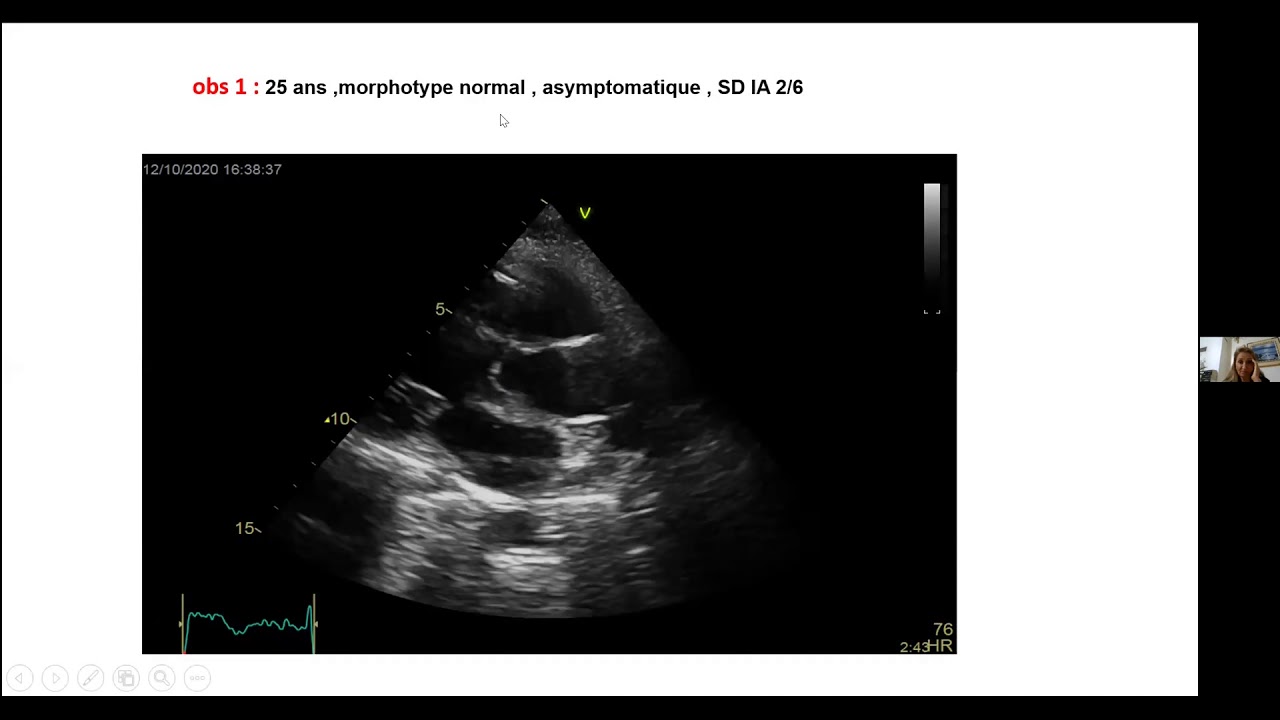

Comment opérer les fuites aortiques sevères? Réparer ou remplacer?

G. El Khoury - S. Chraibi